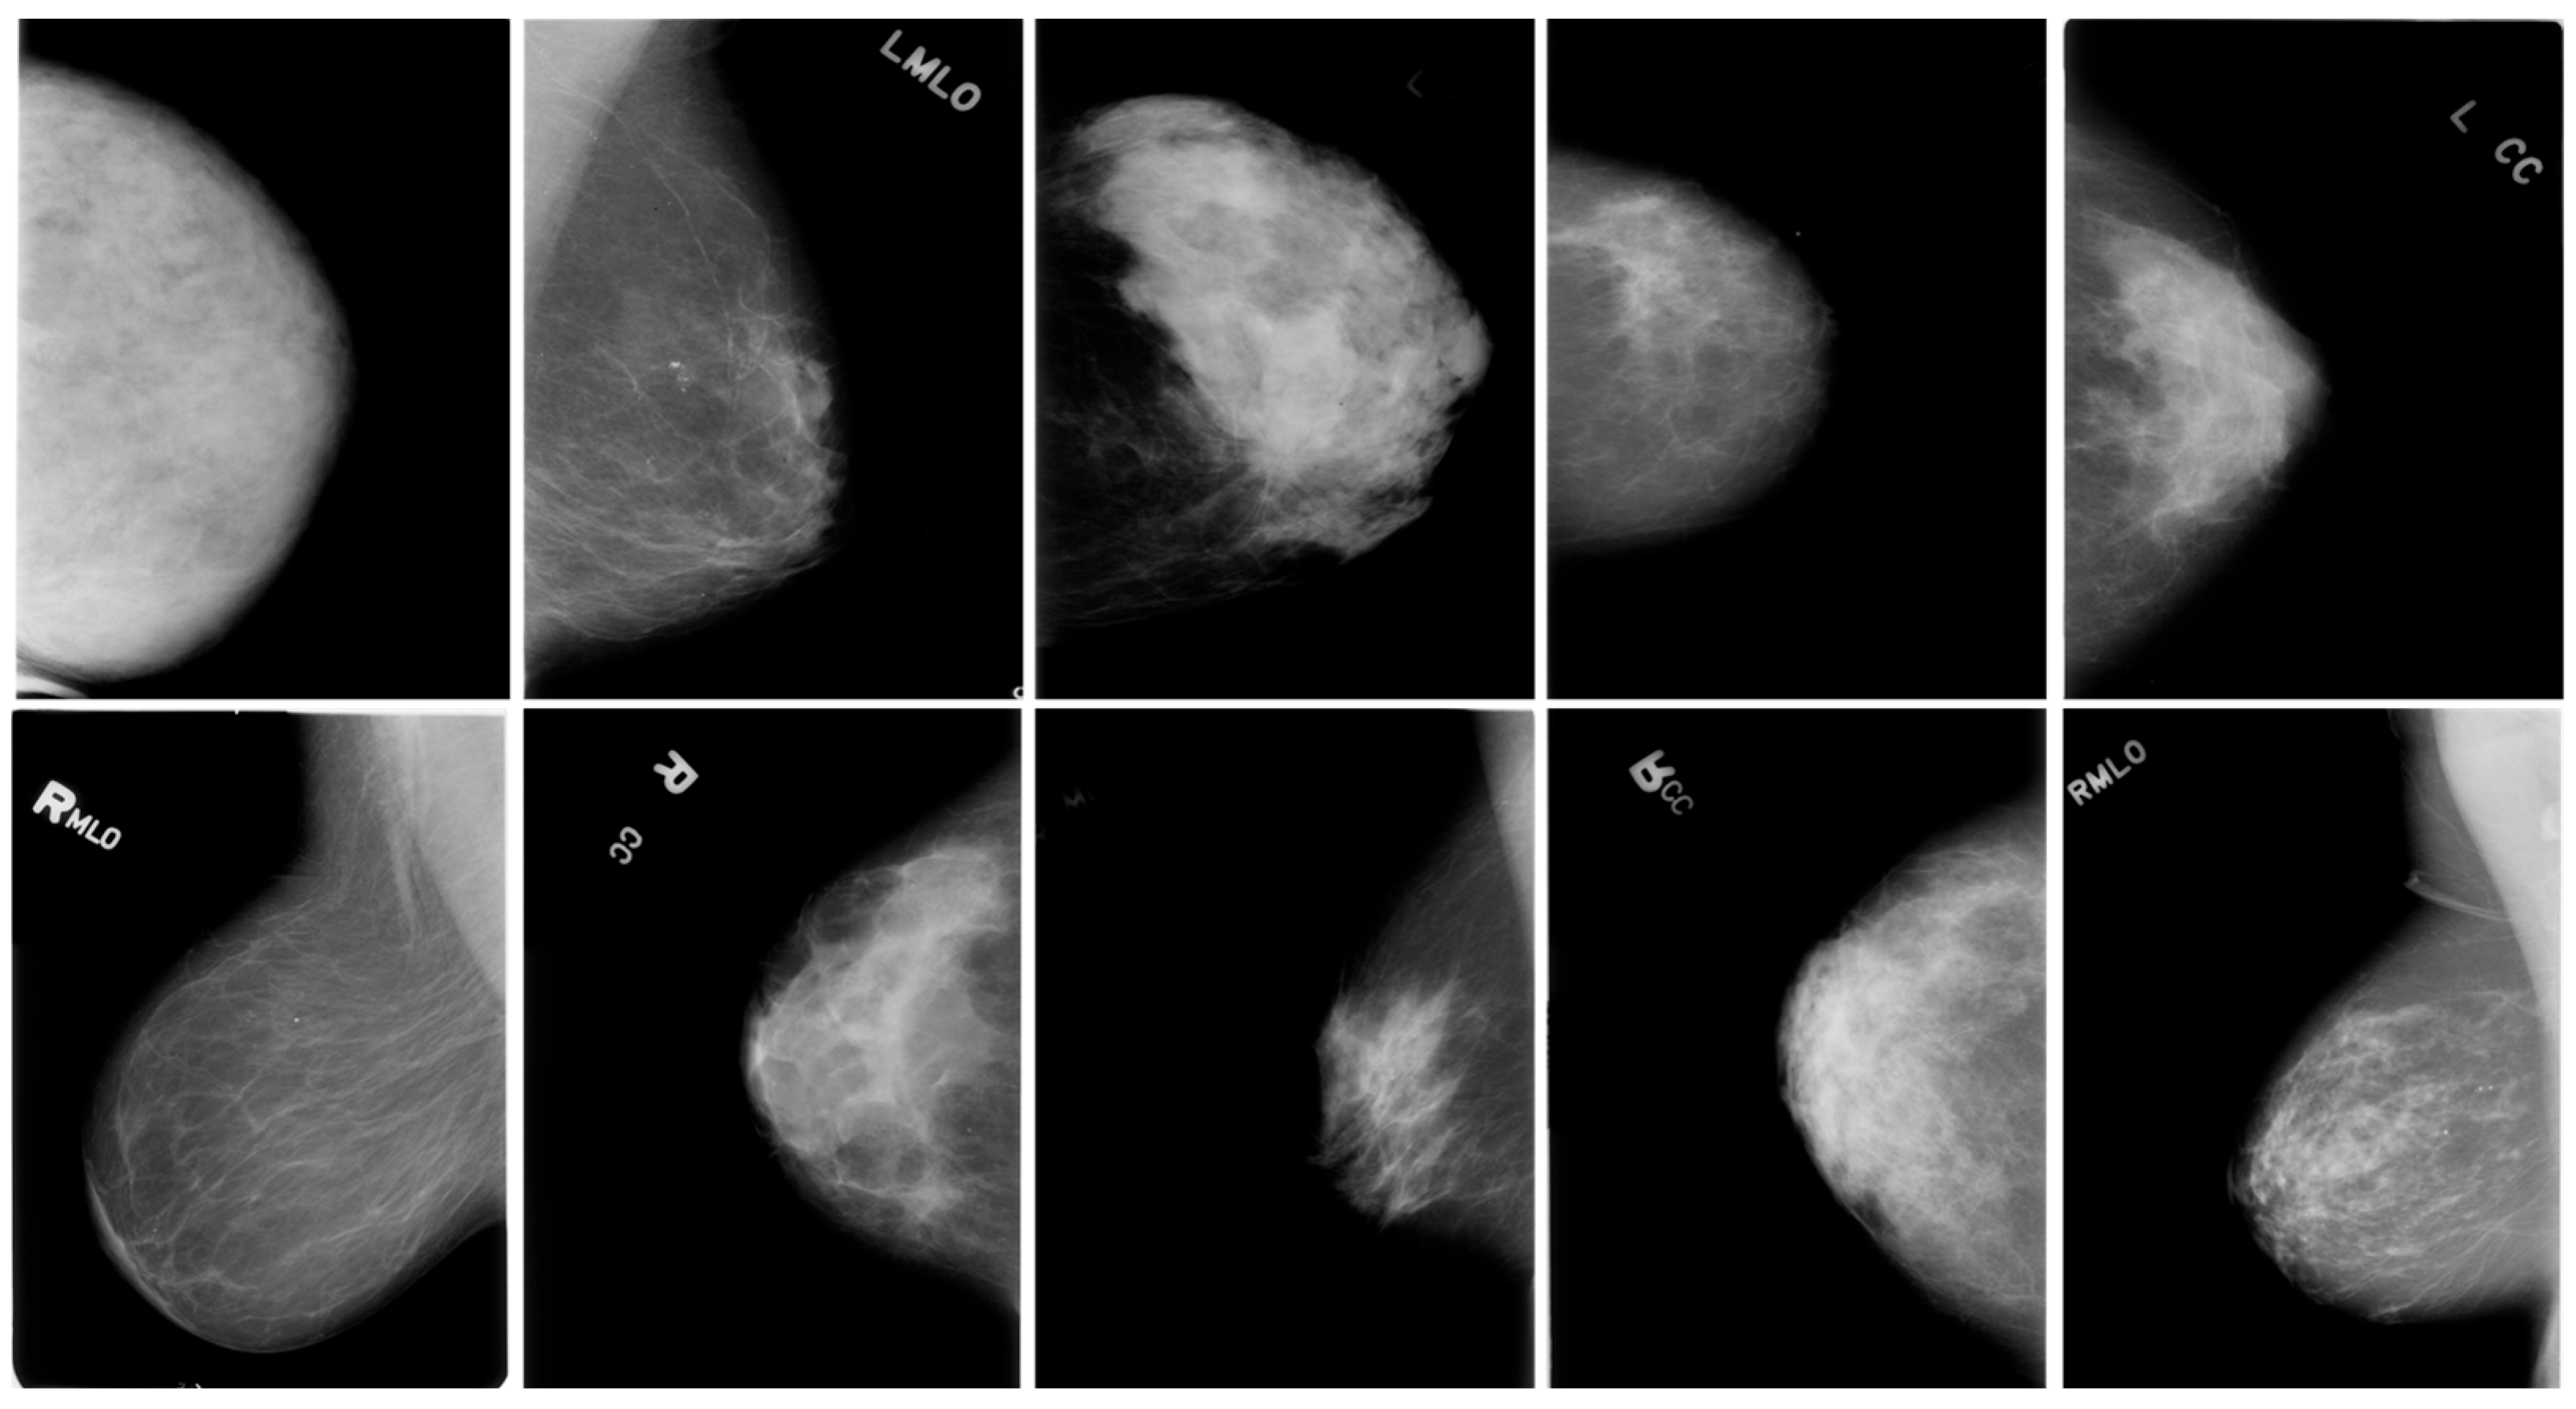

A dataset example is shown in Figure 1.

Figure 1.

Example of dataset images.

The DDSM-CBIS dataset states that the data were separated into test and training sets. The dataset contains both positive and negative state images from the CBIS-DDSM dataset and the DDSM dataset. The data were pre-processed to create 299 × 299 images. Before being downsized to 299 × 299 pixels, the negative images from the DDSM dataset were tiled into the size 598 × 598 pixels before being resized to the size 299 × 299.

The ROIs for the positive images of the CBIS-DDSM dataset were extracted depending on using masks with padding of small values to produce context. Each ROI was then cropped randomly three times into an image size of 598 × 598 pixels, after that, random rotations and flips, before being resized to images with size 299 × 299 pixels.